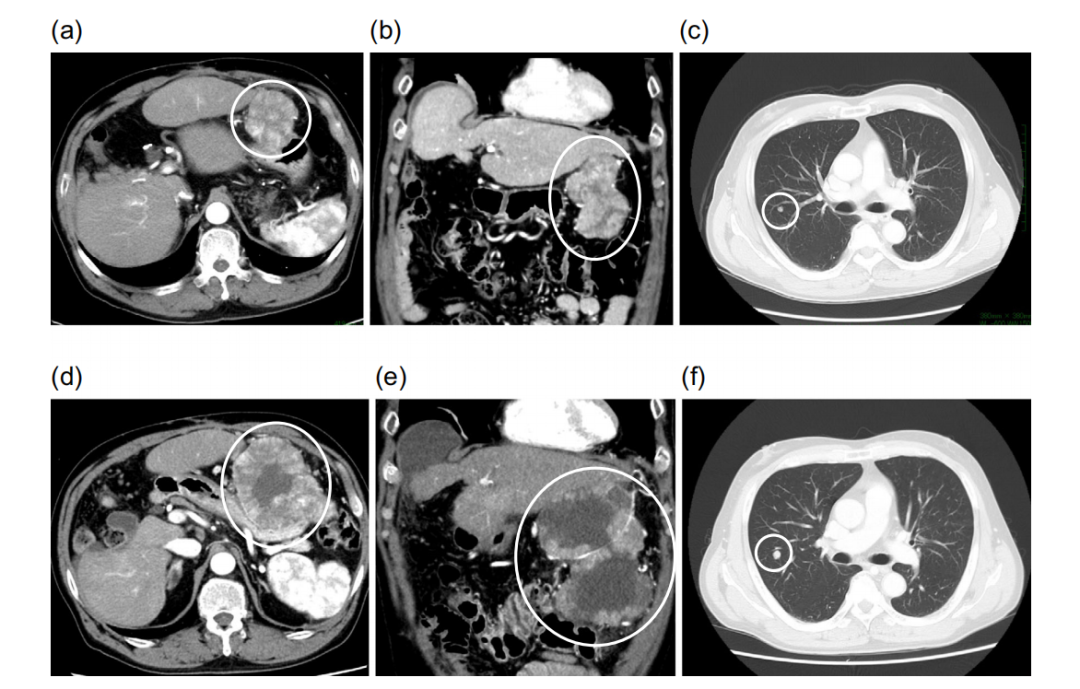

既往手术史

患者因HCC破裂接受了急诊经导管动脉栓塞术(TAE),随后接受了肝第5段部分切除术和肝第6段亚段切除术。肝切除术后6个月,患者因腹膜播散再次在附近医院接受TAE,并行大网膜结节切除术和部分降结肠切除术。第二次手术7个月后,CT显示肝第7节段HCC复发并伴有腹膜播散。经导管动脉化疗栓塞(TACE)治疗肝7段。TACE术后1个月CT显示肝内肝癌复发及肺转移。

瑞戈非尼二线治疗实现降期转化

瑞戈非尼的起始剂量为160mg,每天口服一次,用3周停1周。治疗初期,患者出现3级低磷血症,对症治疗后得到了改善。开始瑞戈非尼治疗 9个月后,由于出现2级手足综合征,暂停使用瑞戈非尼。停用10天后,他重新服用瑞戈非尼,剂量降低为标准剂量的一半,即80mg,每天1次。减少剂量后,没有出现不良事件,所以在减少剂量9个月后,瑞戈非尼的剂量增加到160mg/天。患者在接受瑞戈非尼治疗10个月时病灶就达到部分缓解(PR)。

在瑞戈非尼治疗19个月后,他接受艾尔巴韦和依巴司韦格佐普韦片治疗HCV,并在治疗后12周获得持续病毒学应答(SVR)。瑞戈非尼治疗22个月后,CT显示新的肺转移和腹膜播散增强结节,大小为10mm。PET/CT显示腹膜播散性高代谢病变,最大标准化摄取值(SUVmax)为5.6,而右肺转移灶为2.4。

腹膜播散行手术切除,病理结果为HCC转移。第三次手术后2个月,CT显示肝3段HCC复发,肺转移灶的大小没有变化。HCC为单个小于20mm的结节,接受射频消融(RFA)治疗。肺部转移采用胸腔镜手术(VATS)治疗。距离肝细胞癌破裂已经过去了4年零6个月,基于这些治疗,病人仍然存活。